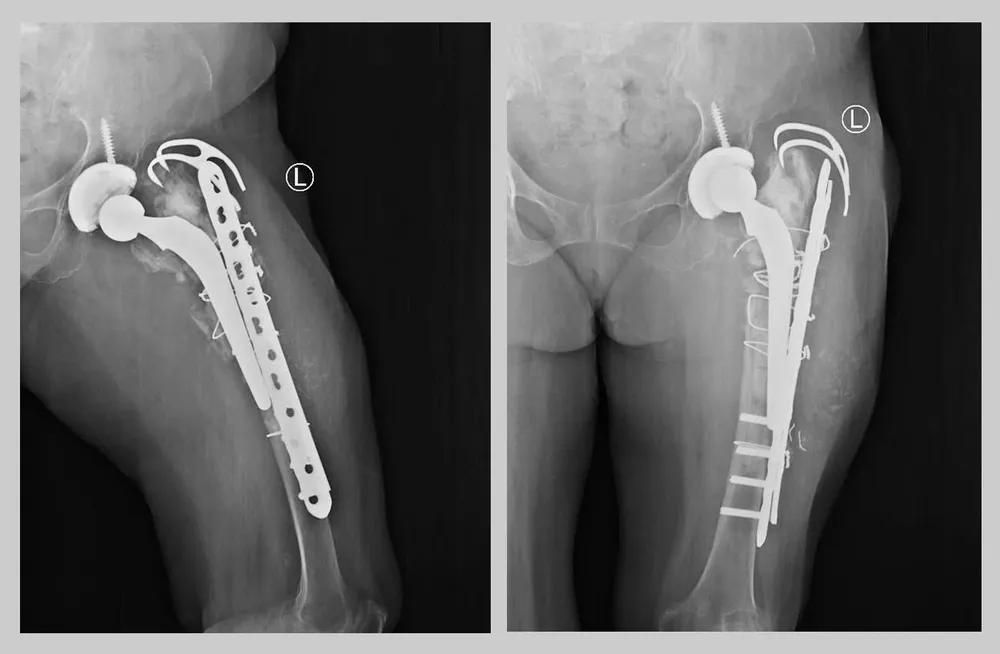

Qua thăm khám và chẩn đoán hình ảnh, các bác sĩ ghi nhận tình trạng tiêu xương lan rộng, gãy quanh khớp háng nhân tạo, gãy phương tiện kết hợp xương, lệch trục và rút ngắn chi trên 7cm – một tổn thương nặng nề và phức tạp, có nguy cơ mất chức năng chi thể nếu không can thiệp kịp thời.

Sau gần 4 giờ đồng hồ với sự hỗ trợ tối đa về nhân lực và trang thiết bị hiện đại, ca mổ thành công, khôi phục cấu trúc và chức năng chi thể, đồng thời phục hồi chiều dài hai chân bằng nhau.